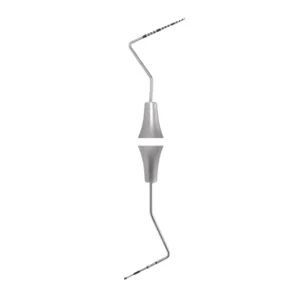

- Double-ended design: This probe has two different ends, allowing for versatility in dental procedures. One end is a universal curette (Unc 15), while the other end is a screening probe (PCP15/11.5).

- High-quality construction: The GDC Double End Probes Unc 15 / Screening Probe #1 is typically made of high-quality stainless steel or other durable materials. This ensures its longevity and resistance to corrosion, enabling repeated use in dental settings.

- Ergonomic handle: The probe’s handle is designed for comfortable gripping and control during dental procedures. This ergonomic feature allows for better maneuverability and reduces hand fatigue during extended use.

GDC Double End Probes Unc 15 / Screening Probe #1 (PCP15/11.5)

GDC Double End Probes Unc 15 / Screening Probe #1 (PCP15/11.5) is a dental instrument used by dentists and dental hygienists for periodontal probing and screening. It consists of a double-ended design with different measurements on each end. The “Unc 15” marking refers to the first end of the probe.UNC15 Probe has markings mm1-2-3-4-5-6-7-8-9-10-11-12-13-14-15 and Screening Probe has markings mm 3.5-5.5-8.5-11.5 inscribed onto the head of these instruments for accuracy and readability.